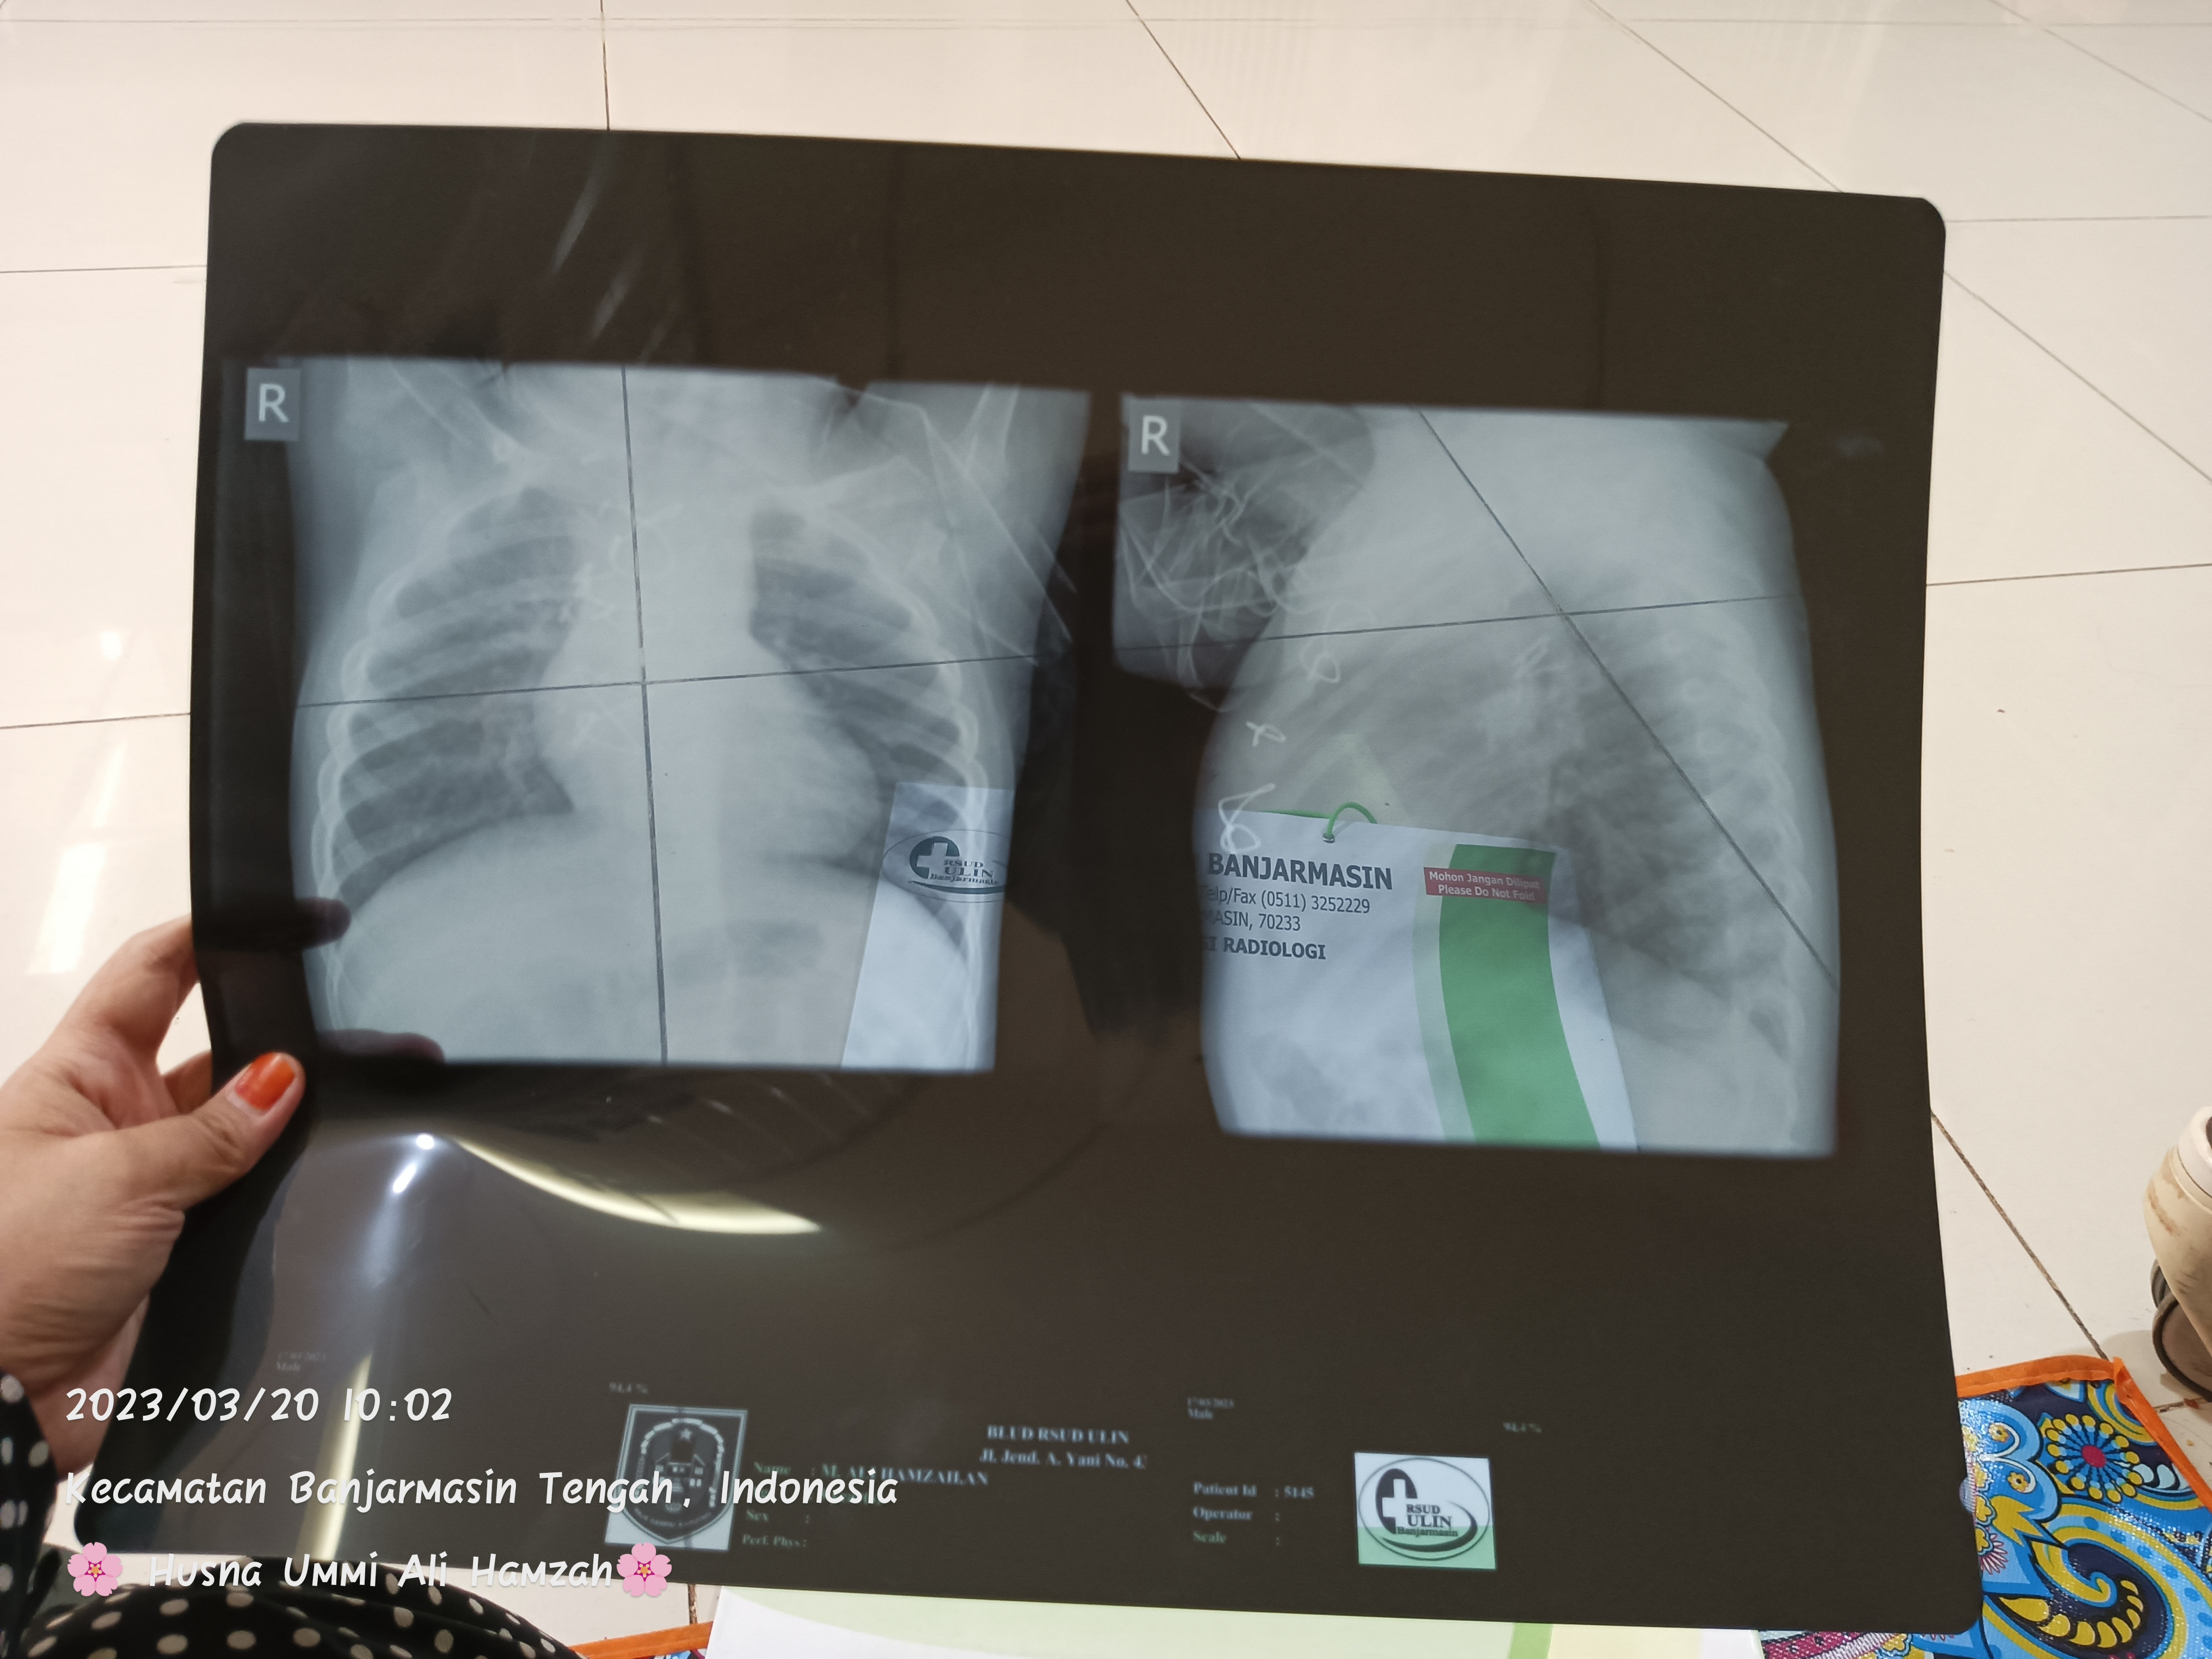

Aku hanya ingin mengabarkan mengenai kondisi “Ali Hamzah” anakku saat ini. Alhamdulillah anakku sehat dan sedang melengkapi beberapa berkas pemeriksaan di Rumah Sakit Daerah seperti echo terbaru dan rontgen terbaru secara rutin setiap Rabu, Kamis dan Jumat sesuai arahan dokter. Doakan anakku ya TemanBaik agar ia sehat selalu dan semoga ada kabar baik untuk hasil rapat bedanya.